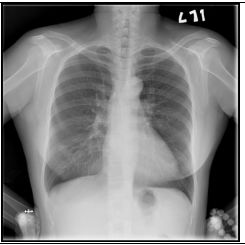

2. A 27-year-old woman had productive cough for one month.